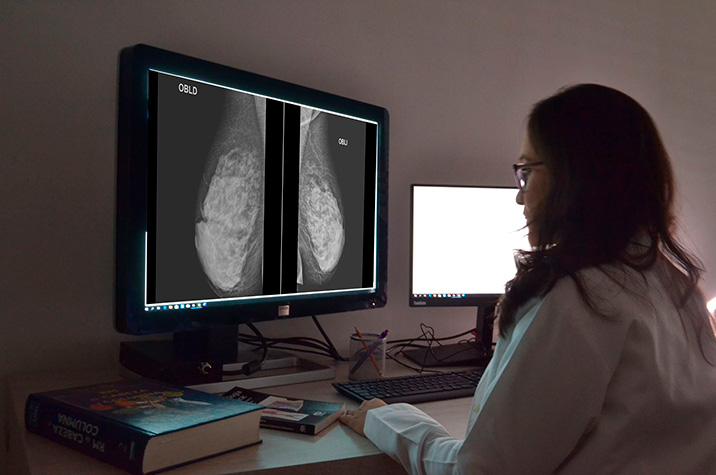

Modificaciones en las guías de rastreo de la USPSTF y cambios en la incidencia del cáncer de mama

En este estudio de cohorte, el cáncer de mama in situ disminuyó desde 2009, en consonancia con la disminución del uso de la mamografía de detección desde los cambios en las directrices de 2009, pero esta disminución no pareció haberse traducido en estadios más avanzados del cáncer de mama en el momento del diagnóstico ni en disminuciones en la proporción de casos tratados con mastectomía parcial. JAMA Network Open , 27 de diciembre de 2024.